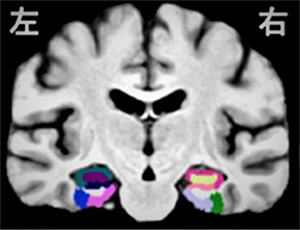

"Mild exercise improves sifting between similar memories"